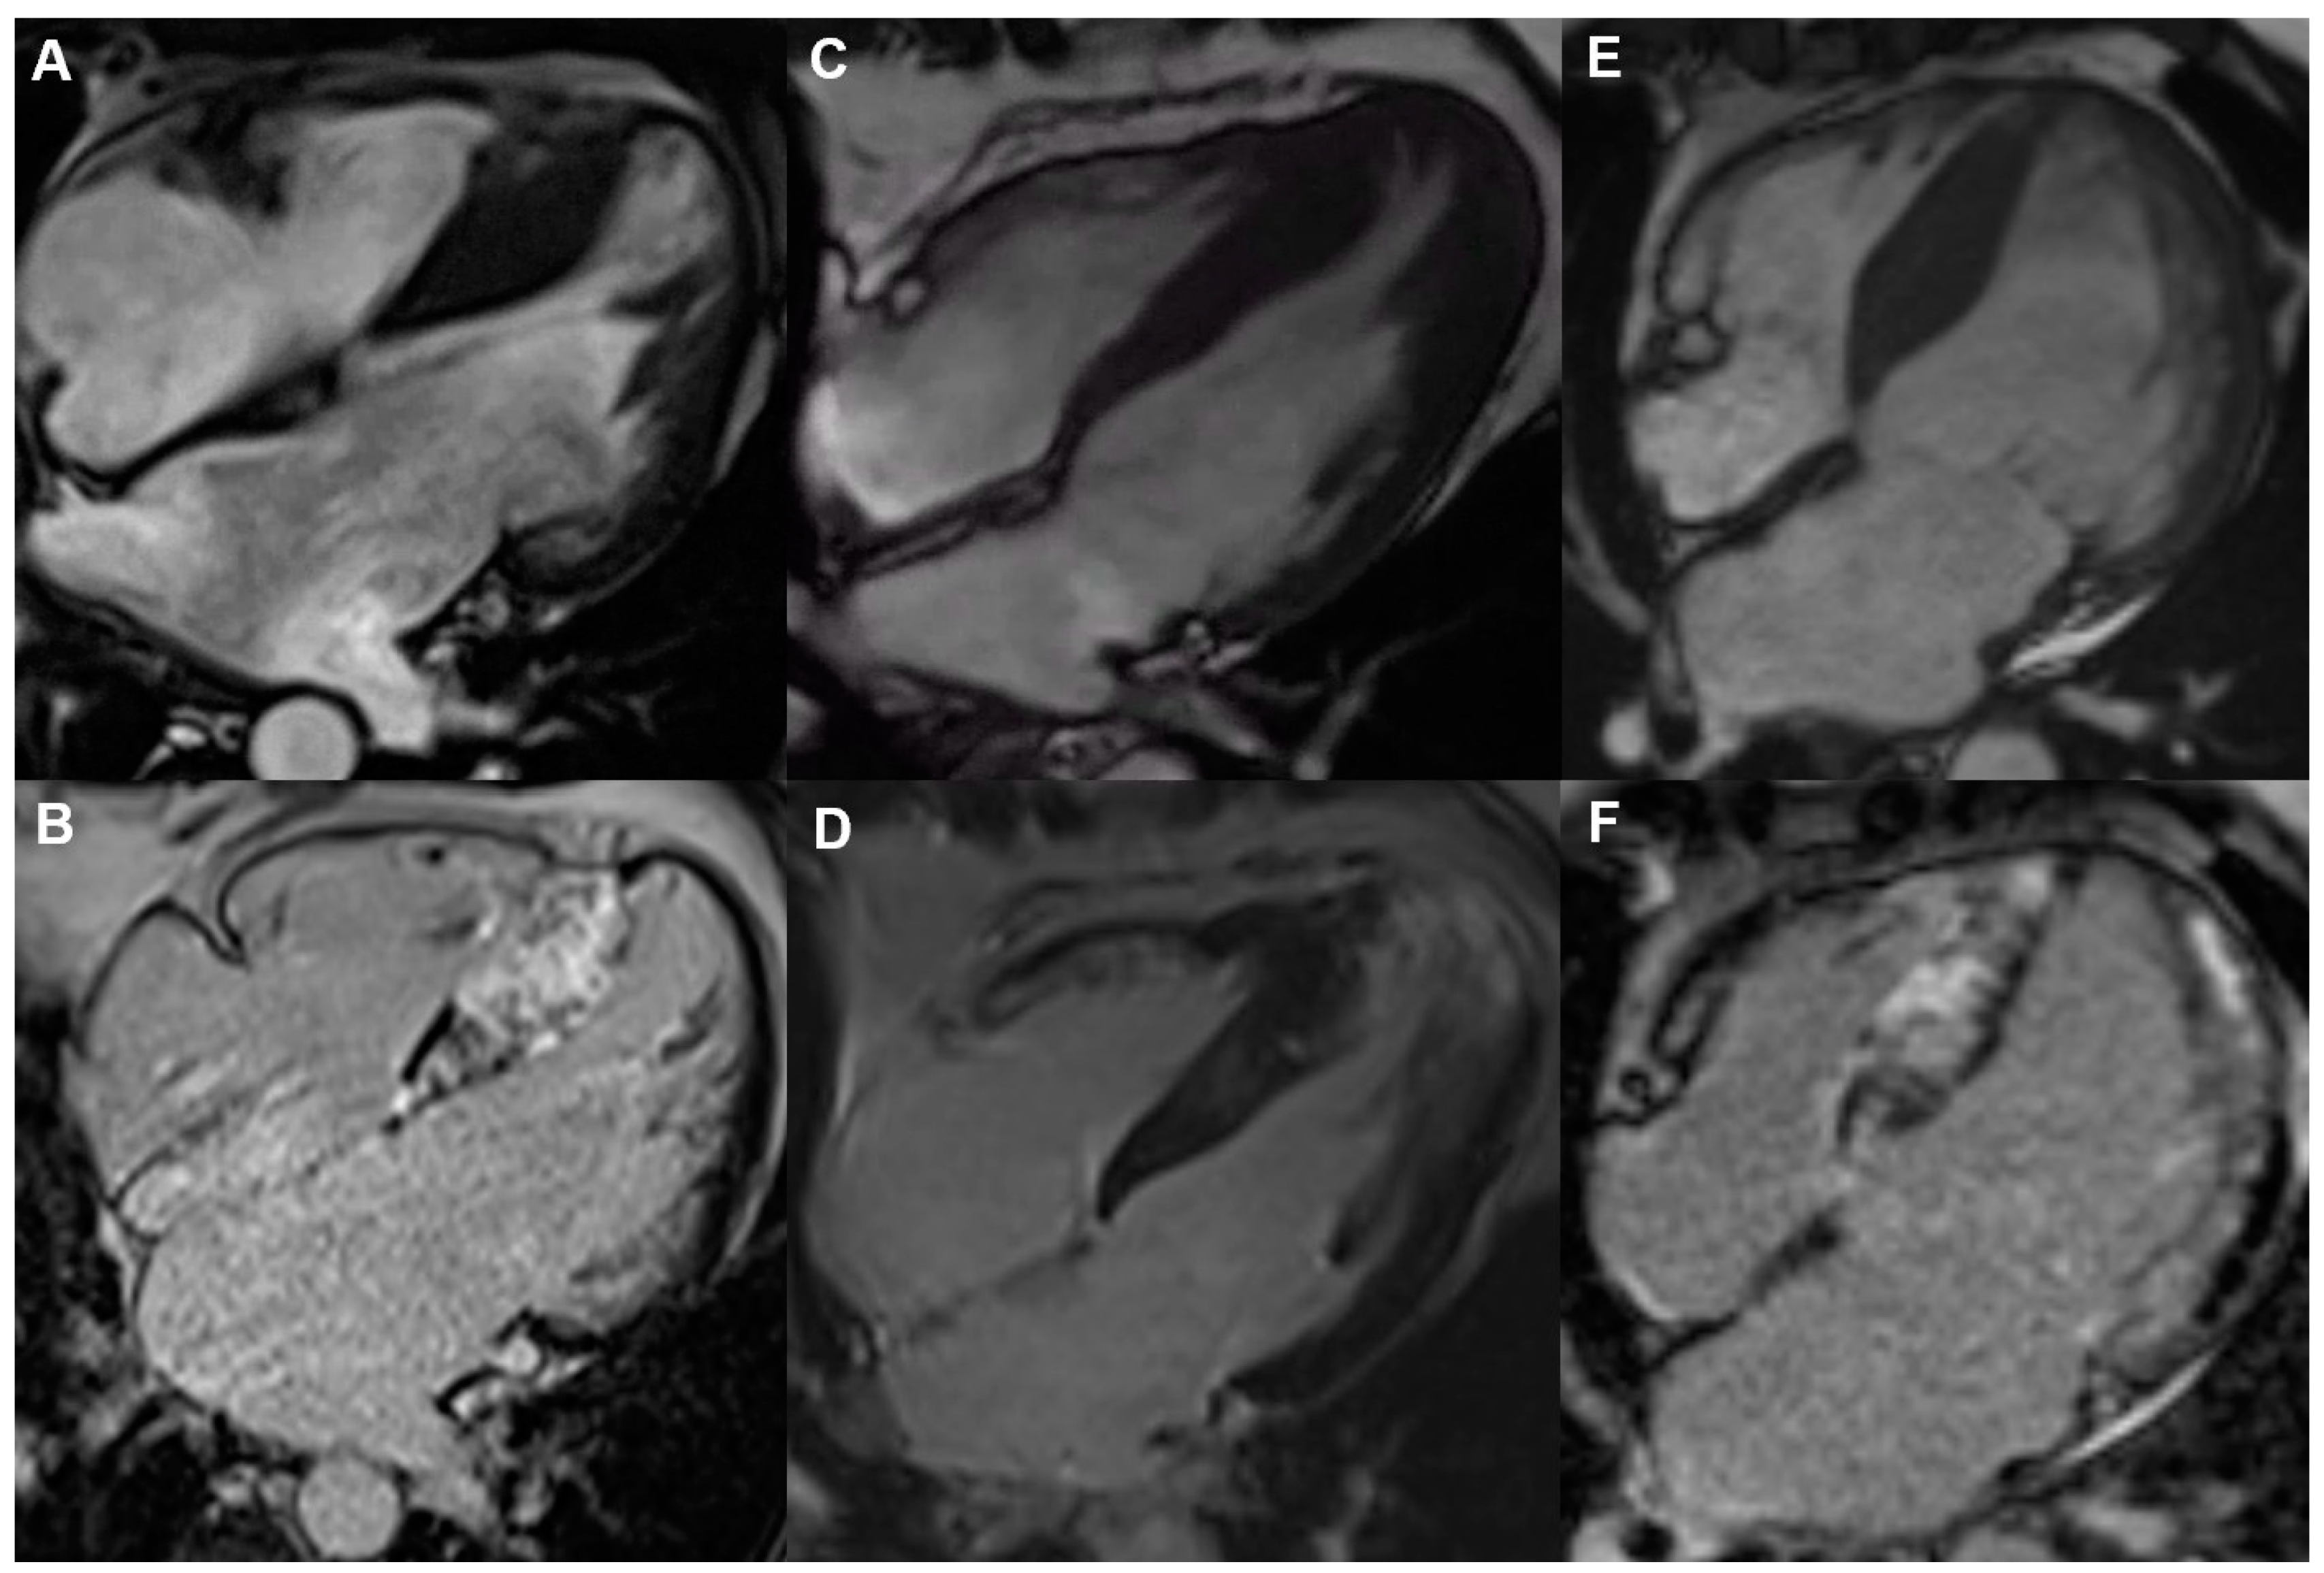

3. Late Gadolinium Enhancement in Cardiac Magnetic Resonance

8.2. Multimodality Imaging